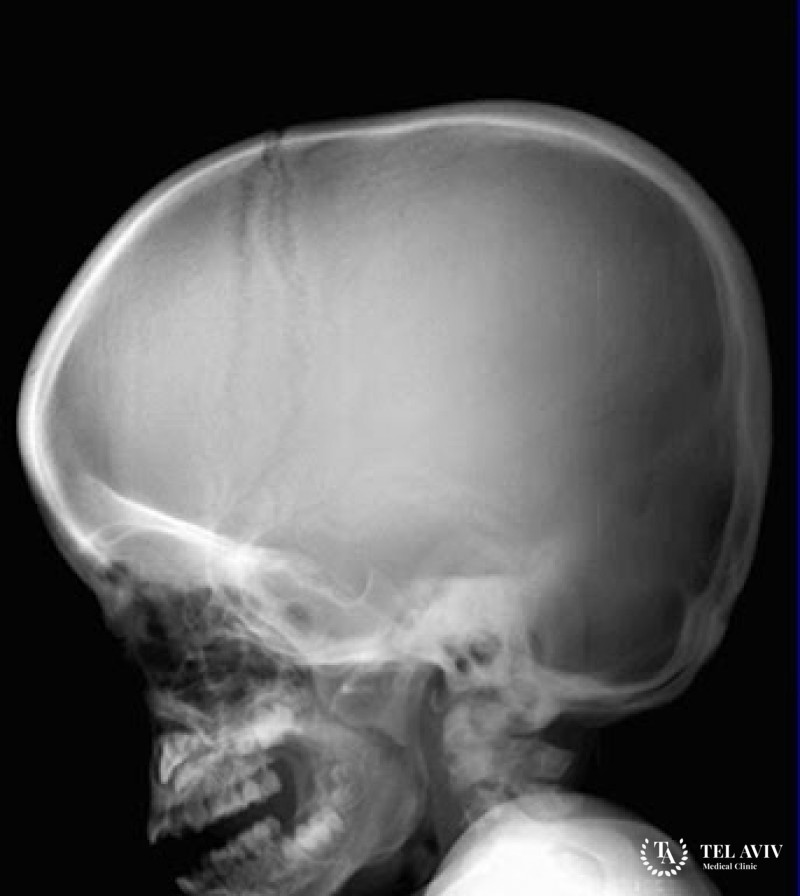

Мукополисахаридоз – является редким генетическим заболеванием, для которого характерен дефицит фермента лизосом, который участвует в катаболизме кислых мукополисахаридов и составляет основу соединительной ткани. Врач может заподозрить наличие патологии во время профилактического осмотра. Для постановки верного диагноза он проводит исследования крови, внутренних органов и генетические тесты.

- Деформация костной ткани;

- Грубые черты лица;